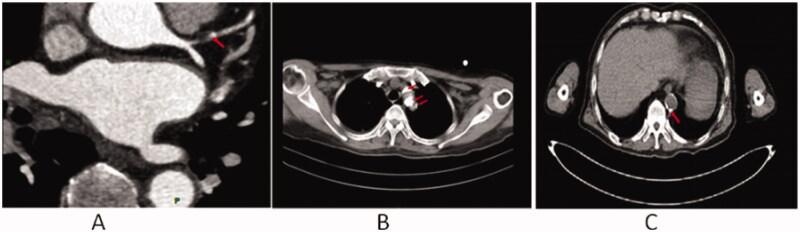

We conducted a cross-sectional study on 293 ESKD patients undergoing combination therapy of hemodialysis and hemodiafiltration at the First Affiliated Hospital of Chongqing Medical University from October 2014 to December 2015. CVC was evaluated echocardiography.

我们对 2014 年 10 月至 2015 年 12 月在重庆医科大学第一附属医院接受血液透析和血液透析滤过联合治疗的 293 例 ESKD 患者进行了横断面研究。通过超声心动图评估 CVC。